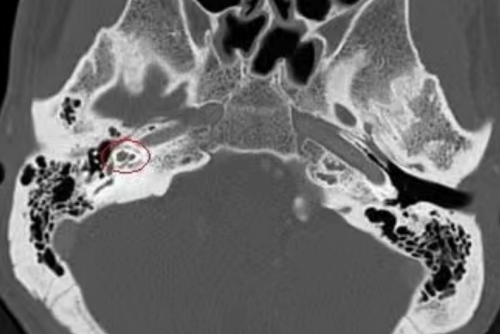

(影像资料提示耳内病灶部位)

诊断明确后,手术团队为刘先生进行“耳内镜下右人工蹬骨植入术”。术中,在进行镫骨底板钻孔时突然出现大量脑脊液井喷,考虑外淋巴液与脑脊液之间存在异常通道的可能,而耳硬化症并发脑脊液耳漏在临床上极为罕见,文献中也仅有零星报道,立博体育 也是首次遇到镫骨打孔后脑脊液井喷的情况,无疑给手术带来更大的挑战和难度。冯永教授凭借丰富的临床经验和精湛的技术成功取出原来已经固定的病变镫骨,并封闭前庭窗修复脑脊液耳漏后植入人工镫骨,整个过程如履薄冰,手术顺利完成,术后刘先生初测听力明显好转,没有脑脊液耳漏和眩晕的情况,过几天即可出院回家。